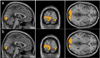

Arterial-spin-labeling (ASL) magnetic resonance imaging (MRI) provides a noninvasive tool to measure cerebral blood flow (CBF) and is increasingly used as a surrogate for baseline neural activity. However, the power of ASL MRI in detecting CBF differences between patient and control subjects is hampered by inter-subject variations in global CBF, which are associated with non-neural factors and may contribute to the noise in the across-group comparison. Here, we investigated the sensitivity of this technique and proposed a normalization strategy to better detect such a difference. A "model" situation was employed in which two visual stimuli (i.e. cross fixation and flashing checkerboard) were presented to two groups of subjects to mimic "control" and "patient" groups (N=7 for each group), respectively. It was found that absolute CBF (aCBF) in the occipital lobe in the checkerboard group was 26.0% greater compared to the fixation group, but the level of significance was modest (P=.03). In contrast, when normalizing the CBF with whole-brain CBF or CBF in a reference region [termed relative CBF (rCBF)], the statistical significance was improved considerably (P<.003). For voxel-based analysis, the rCBF indices correctly detected CBF differences in the occipital lobe in the across-group comparison, while aCBF failed to detect any significant cluster using the same statistical threshold. We also performed Monte Carlo simulation to confirm the experimental findings and found that the power improvement was most pronounced when signal-to-noise-ratio is moderate and the underlying CBF difference was small. The simulation also showed that, with the proposed normalization, a detection power of 80% can be achieved using a sample size of about 20. In summary, rCBF is a more sensitive index to detect small differences in CBF, rather than the much-sought-after aCBF, since it reduces data noise caused by inter-subject variations in global CBF.